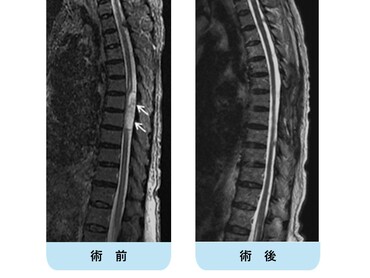

術前MRIでは多椎間で脊髄(灰色)を圧迫しています。後方手術施行後、脊髄への圧迫は改善しています。